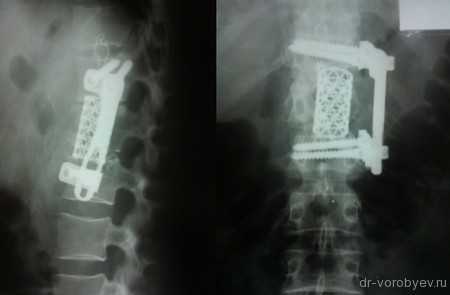

Пациент с неспецифическим спондилодисцитом в грудном отделе позвоночника

Выполнена операция торакотомия, трансплевральная корпорэктомия, комбинированный корпородез аутокостью и пластиной Centaur фирмы Stryker